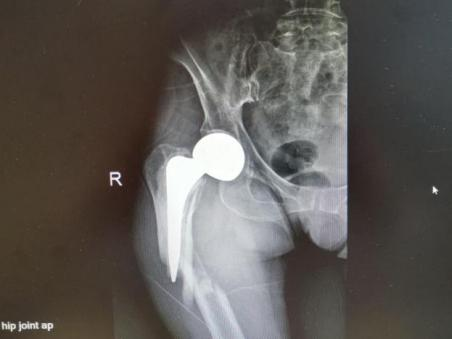

多年来,贵州航天医院各科室紧跟医学前沿,不断强技术、补短板,大力开展新技术、新项目,完成了许多高精尖、高难度、本地区“首例”的技术,填补了医院医疗技术空白,满足了群众日益增长的医疗需求。 贵州航天医院骨科率先在遵义地区开展骨搬移技术,截至目前,已治愈慢性骨髓炎、感染性骨不连、骨缺损、脉管炎、糖尿病足患者200余例,糖尿病足治疗保肢率达到98%。 本期,我们将为大家带来骨科特色技术——骨搬移技术(Ilizarov)。 案例分享 一名59岁的患者,身患糖尿病12年,在来我院3个月前出现了右脚溃烂的症状,来院就诊时,患者的右脚十分红肿,右脚脚趾坏死,伤口处不断流出黑红色脓液,情况十分严重。在接诊到患者时,骨科专家团队高度重视,立刻为患者完善了CT血管造影(CTA)等相关检查,诊断为:2型糖尿病,糖尿病周围血管病变,右糖尿病足。 术 前 考虑到患者情况比较严重,为最大限度保证患者肢体完整,科室专家团队进行了严格的讨论评估,为患者制定了骨搬移技术治疗方案,在征得患者及其家属的同意后,成功通过搬移骨块为患者进行治疗,促进患者病变肢体血管再生。 胫骨横向骨搬移外架固定 清除感染病灶 术后调节外架,通过搬移骨块 促进患肢血管再生 患者在术后三周前来换药,观察到感染得到进一步控制;术后六周复查,患者病变处已愈合,进行CT血管造影(CTA)后可明显观察到足部血管再生。 术后3周 术后6周愈合 CT血管造影见足部血管再生 糖尿病患者全身与局部的问题互为影响,形成恶性循环,糖尿病足溃疡创面迁延不愈,常见干性坏疽、湿性坏疽、趾坏死、深且大的溃疡以及骨髓炎等症状,还可导致脓毒血症,以往为保全生命,患者被迫选择一次或多次截肢。骨搬移技术的发展进步,能在血糖有效控制、局部有效清创下,有效促进患肢微血管再生,改善患肢血供,达到糖尿病足更快治疗康复的目的,并能根据病变情况最大限度的保障患者肢体完整。 什么是骨搬移技术 骨搬移技术是通过使用专用的骨外固定器固定骨段,每天缓慢牵拉,在牵拉搬移过程中,骨段尾部形成新骨及新的软组织,从而修复骨骼缺损及软组织缺损。是治疗大段骨缺损、骨不连、骨感染、肢体畸形的金标准方法,也用于治疗脉管炎、糖尿病足等肢体缺血性疾病。 骨感染缺损 切除感染段 搬移骨段 新骨形成 骨感染根治愈合 骨搬移技术原理 生物组织在持续、稳定、缓慢牵拉下,能刺激细胞分裂、组织再生,骨外固定技术运用该原理,通过持续缓慢调节外固定器形成牵拉张力,促进牵引成骨与相邻组织再生,如神经、血管、肌肉、皮肤等再生,达到治疗大段骨缺损、肢体缺血如糖尿病足等疾病的目的。 骨搬移技术优势 (一)除治疗骨缺损、骨不连外,有更广的适用范围,利用组织再生、血管再生等特性,能大量运用于肢体畸形的矫形、糖尿病足等的治疗。 (二)治疗效果确切,重建肢体外型和功能,极大降低截肢率和残疾率。 (三)明显提高了患者生活质量,极大减轻其家庭及社会负担。 肢体畸形的矫形 慢性骨髓炎 骨段切除 术后1年 濒临截肢的脉管炎术后6周 难愈创面术后3周 贵州航天医院骨科 专家团队 赵学平 骨科主任 主任医师 临床擅长:从事骨科临床工作30余年,对骨科常见疾病的诊治具有丰富的临床经验。 世界中医药联合会脊柱康复专业委员会常务理事,中华中医药学会整脊分会常务委员,中国中西医结合学会骨伤科分会肢体矫形功能重建与康复专家委员会常务委员,中国研究性医院学会骨科创新与转换专业委员会关节外科学组保髋工作委员会常委,中国康复技术转化及发展促进会骨外科与康复技术转化专业委员会常务委员,泛珠三角区域运动医学联盟(PPRD-SMA)理事会常务理事,中国研究型医院学会运动医学专业委员会委员,贵州省中医药学会整脊分会副主任委员,贵州省中西医结合学会银质针专业委员会副主任委员,贵州省康复医学会骨与关节专业委员会常务委员,贵州省人民医院骨科专科联盟常务理事,贵州省康复医学会骨内科专业委员会常务委员,中华医学会贵州省骨科学会委员,贵州省康复医学会脊柱脊髓专业委员会常务委员,贵州省运动医学分会委员,贵州省康复医学会骨与软组织肿瘤专业委员会委员,遵义市医学会创伤分会副主任委员,贵州省康复医学会骨内科专业委员会遵义地区分会常务委员,遵义市医疗事故鉴定、伤残鉴定、工伤鉴定、司法鉴定专家。 长期从事骨科临床研究及教学工作,在国家级、省部级杂志发表论文20余篇,SCI论文2篇,参与主编骨科专著2部,主持省部级科研项目2项,参与指导省部级、市级科研项目6项。 陈明勇 骨科副主任 副主任医师 临床擅长:从事创伤骨科工作约20年,对骨缺损、骨不连、骨肿瘤、肢体畸形等的肢体矫形重建及功能重建,慢性化脓性骨髓炎的根治治疗、糖尿病足的保肢治疗、快速康复理念(ERAS)下的老年骨折的诊治,四肢复杂骨折的诊治,四肢骨折等微创手术治疗具有丰富的临床经验。 2004年毕业于遵义医学院临床专业,曾在中国人民解放军总医院、广西医科大学第一附属医院、上海第六人民医院骨科进修。中国中西医结合学会骨伤科专业委员会横向骨搬移治疗糖尿病足及微血管网再生学组首届委员,遵义市医学会创伤分会常务委员。 瞿 辉 骨科 副主任医师 临床擅长:对骨科的常见病、关节外科、脊柱外科及运动医学疾病的诊治具有丰富的临床经验,熟练掌握骨科手术操作技术。 毕业于遵义医学院临床医学系,2005年前往广州中山大学第一附院骨显微医学部进修学习,2011年前往成都华西医院进修学习,并多次在省内外学习骨科相关知识,是中华医学会骨科分会会员。 赵兴东 骨科 主任医师 临床擅长:擅长骨科的常见病及各种创伤、四肢骨折创伤修复、骨感染、手足疾病的诊治和手足体表畸形的矫形整复,熟练掌握骨科四肢骨病及创伤的手术操作技术,尤其在四肢关节复杂性损伤、手足外伤、组织缺损创面、难治创面的皮瓣修复方面及平足、高弓足矫形方面及四肢慢性疼痛诊治、康复方面具有丰富的临床经验。 硕士研究生,毕业于遵义医学院临床外科系,2015年前往山东省立医院手足外科进修学习;遵义市医学分会创伤分会第一、二届委员,遵义市手外科医学会第二委届员会常务委员;在省级及省级以上期刊发表文章9篇,参编著作2部,参与主持并完成市级课题1项,参与市级课题2项、省级课题1项。 张俊凯 骨科 副主任医师 临床擅长:从事骨科临床工作28年,对创伤骨折、骨感染、骨缺损、骨不连等外科诊治,四肢骨折的微创手术治疗,四肢复杂骨折(如关节内粉碎性骨折、多发骨折等)的损伤控制及手术治疗等具有丰富的临床经验。 1995年毕业于遵义医学院临床专业,2009年前往复旦大学附属医院骨科进修1年。 卢懿明 骨科 副主任医师 临床擅长:从事骨科工作18年,对创伤骨折、四肢骨折的微创手术治疗、四肢复杂骨折(如关节内粉碎性骨折、多发骨折等)的损伤控制及手术治疗,尤其是髋部骨折的PFNA等微创技术,踝关节骨折、膝关节周围骨折的Mipo微创技术等具有丰富的临床经验,开展了4项新技术,发明6项新型专利技术。 2005年毕业于遵义医学院临床专业,2017年,前往南方医科大学第三附属医院骨科进修半年,回院后运用Mipo技术对骨干骨折及干骺端骨折的治疗技术,同时积极开展骨盆骨折、髋臼骨折腹直肌外侧切口的应用;发表了多篇专业论文,经常参与省内外学术交流会授课,获得医院荣誉称号多个。 邬夏荣 骨科 副主任医师 临床擅长:从事骨科工作16年,对四肢复杂骨折、骨肿瘤的诊治,尤其是足踝创伤、慢性踝关节损伤、平足症等诊疗具有丰富的临床经验。 2006年毕业于遵义医科大学临床医学专业,曾在陆军军医大学西南医院进修学习,发表多篇骨科学术论文。 余德怀 骨科 副主任医师 临床擅长:从事骨科工作10余年,对运动医学、骨关节、脊柱外科常见病、多发病的诊治具有丰富的临床经验。 硕士研究生,2011年毕业于遵义医学院临床医学专业,曾前往遵义医科大学附属医院运动医学专业进修学习;是贵州省医学会运动医学分会青年委员,西部关节镜联盟委员;发表多篇骨科学术论文。 冯 乾 骨科 副主任医师 临床擅长:从事骨科工作近20年,熟练掌握骨科多发病及常见病的诊治,尤其对脊柱退变性疾病的诊断及治疗具有丰富的临床经验,主要研究脊柱微创相关治疗方式,能熟练开展椎间孔镜及VBE。 曾前往北京大学第三医院进修学习疼痛及椎间孔镜、首都医科大学友谊医院专业进修脊柱内镜;是贵州省康复医学会第三届脊柱脊髓专业委员会委员;发明专利3项、发表脊柱外科专业论文多篇。 张艳金 骨科 副主任医师 临床擅长:从事骨外科工作16年,对复合伤、多发伤的救治、四肢骨干骨折、关节周围骨折、骨肿瘤、骨髓炎等诊治具有丰富的临床经验。 中共党员,硕士研究生,2006年本科毕业于山西医科大学第二临床医学院,2011年研究生毕业于北京军区总医院;在“老年COPD患者合并髋部骨折的诊治”国际合作课题组研究两年,在老年髋部骨折的诊治方面具有丰富的经验,并发表论文6篇;承担遵义市级课题1项;承担遵义医科大学的临床教学工作,获得遵义医科大学优秀带教老师荣誉。编撰有《骨科疾病诊疗精粹》一书,开展2项新技术,编撰地方规范《务川自治县创伤骨科常见疾病诊疗规范》一书。 赵小锋 骨科 副主任医师 临床擅长:从事骨科临床工作11年,对骨科常见病、多发病诊疗有较为丰富的临床经验,擅长脊柱相关疾病诊断及治疗,尤其是颈、腰、腿疼痛疾病诊断及治疗,擅长胸腰椎骨折微创经皮穿刺内固定术、经皮穿刺椎体成形术、经皮穿刺脊柱内镜下腰椎间盘摘除术、单纯开创腰椎间盘摘除术、腰椎滑脱复位椎间植骨椎融合内固定术、腰椎管狭窄减压融合内固定术及人工髋、膝关节置换术等。 2012年毕业于遵义医学院外科学专业硕士研究生,2019年参加“遵义市115医学人才精英计划”于上海交通大学第一附属医院培训学习,2023年于北京大学第三人民医院脊柱外科进修学习,曾获得遵义市优秀医师荣誉称号。 遵义市手外科第一届委员,遵义市医学会创伤分会第一届委员,遵义市医学会创伤分会第二届委员,贵州省康复医学会第三届脊柱脊髓专业会委员,遵义市医学会烧伤与整形外科学分会委员,发表论文5篇,其中国家级核心期刊1篇,SCI论文1篇,主持市级课题1项并结题,参与市级课题2项。 贵州航天医院骨科简介 基本情况 贵州航天医院(原3417医院)骨科组建于1968年,前身是以创伤和断肢(断指)再植闻名于世的上海市第六人民医院骨科,中国断肢(断指)再植的奠基者、中科院院士陈仲伟等著名专家、学者多次莅临科室指导医疗、教,是贵州省最早拥有专业骨科技术科室之一,在70年代开展了贵州省首例断肢(断指)再植手术。组建50余年来,诊治患者已逾百万,挽救了无数的伤病员,成为了保障遵义地区人民群众健康的重要支撑。 经过几代人的不懈努力,今天的骨科,已由创伤骨科发展至骨病、骨肿瘤、骨结核等领域,现有脊柱外科、关节外科、四肢创伤、手足外科四个亚专科,成为了集医疗、教学、科研于一体的综合学科,是贵州省临床重点专科、遵义市临床重点专科、遵义市骨科临床医学中心、遵义市基层骨科专科联盟理事长单位。 科室目前开放床位110张,共有医护人员50余人,副高级以上专家18人,硕士研究生15人。拥有一流骨科医疗设备多台,每年不定期选派优秀技术骨干到全国各大知名医学院校进修、学习、参观、交流,并邀请国内、国外知名专家教授来院进行交流、指导,通过不断引进国内外先进的诊疗技术,科室医疗技术水平稳步提升,为广大人民群众提供了优质的医疗服务。 专科特色 骨一科 (一)骨缺损、骨不连的肢体与功能重建 胫骨横向骨搬移技术治疗糖尿病足: (二)慢性骨髓炎的根治治疗 (三)肢体缺血性疾病如糖尿病足、脉管炎的保肢治疗 (四)皮瓣修复 (五)复杂创伤的治疗 (六)老年髋部骨折及小儿骨折快速手术 老年髋部骨折: 骨二科 (一)胸腰椎骨折微创经皮椎弓根螺钉固定术 (二)老年性骨质疏松性患者腰椎滑脱脊柱内固定术(骨水泥螺钉) (三)V形双通道脊柱内镜技术(VBE)腰椎融合术治疗腰椎退行性疾病 (四)老年性骨质疏松性骨折(PVP/PKP)术 (五)人工髋关节置换术 (六)双侧股骨头坏死人工全髋关节置换 (七)右侧全髋置换术后假体周围骨折翻修 (八)人工膝关节置换术 (九)人工膝关节假体松动翻修 (十)关节镜技术 传统手术切口 关节镜技术切口 诊疗范围 骨一科 1.四肢创伤、矫形。 2.手、足踝外科。 骨二科